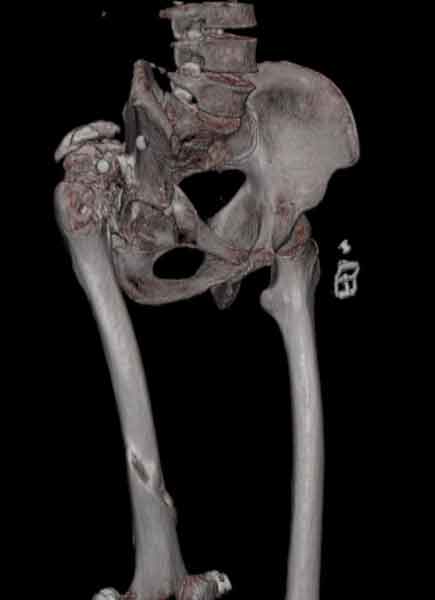

Уважаемые коллеги, пациент 30 лет, 4 года назад попал под поезд, ампутация обеих голеней в в/3, подвздошный вывих бедра (теперь застарелый). несмотря на такую ситуацию, пациент вполне прилично ходит и объем движений в неоартрозе близок к неповрежденной стороне. Основная жалоба - боль при нагрузке и в покое. Планируем двухэтапное лечение: резекция шейки, мобилизация проксимального отдела бедра, низведение бедра АВФ, вторым этапом б/ц эндопротезирование. Как поступить с головкой, вроде бы при протезировании можно будет обойтись без пластики, или ошибаюсь? Оставить ее там, где она есть? Другие варианты лечения.